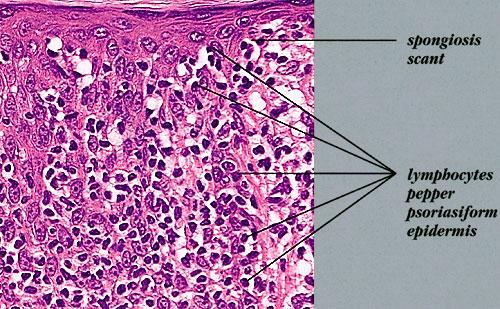

Mycosis Fongoïde =التفطر الكمئي